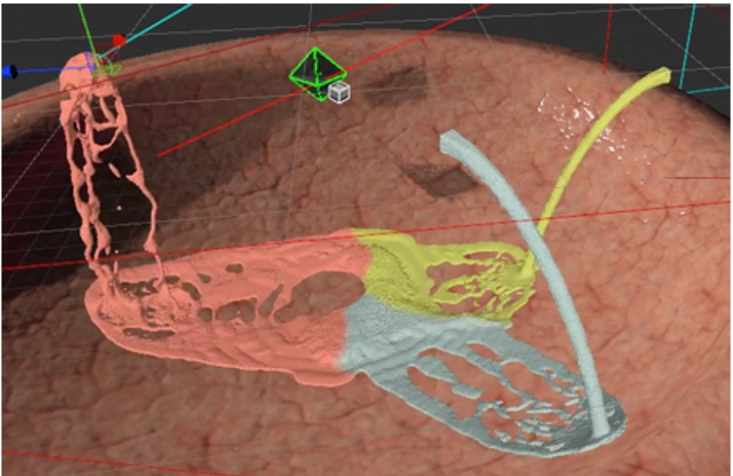

Digital Twin Patient

Realistic, varied anatomy for training and R&D.

• Broad anatomical variations (synthetic + patient-derived)

• Digital twins enhanced with physical properties (beyond 3D geometry)

• Patient-specific rehearsal is in development and will be offered subject to regulatory review

Different methods to create Digital Twin Patients